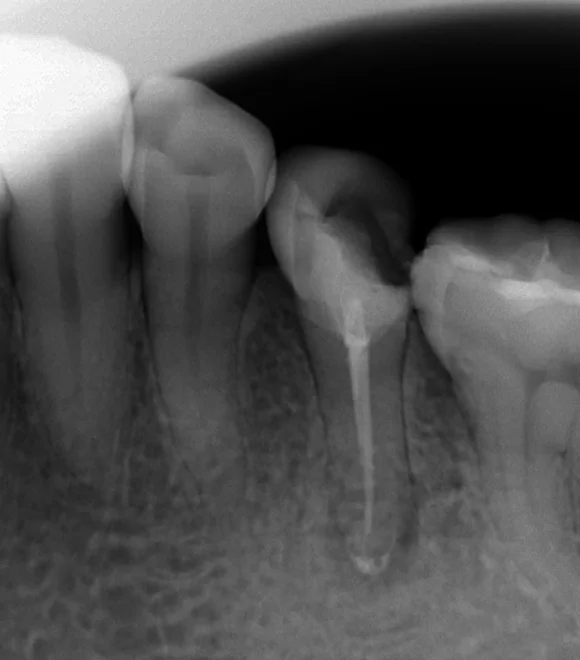

ちょうど真ん中の歯になりますが、歯の後ろ半分に欠けてしまった詰め物が入っています。

そしてそれでいて、根の先に膿が溜まってしまっていますね。(図の赤の部分)

ようやく治療が完了した!と思ってせっせと定期検診を行っていても、ここまで虫歯が進んでしまっては意味がありません・・・。